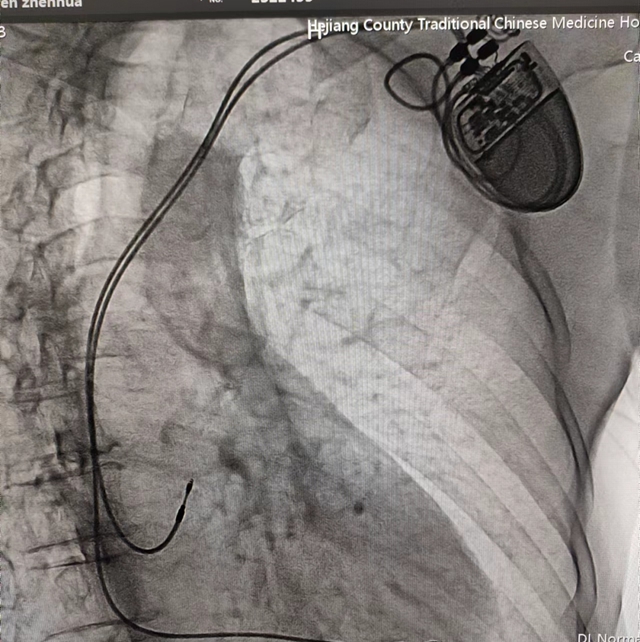

合江縣中醫(yī)醫(yī)院:零突破!3例心臟人工永久雙腔起搏器植入術(shù)成功開展

近日,合江縣中醫(yī)醫(yī)院心血管內(nèi)科成功為3位高齡心動過緩患者植入人工永久雙腔起搏器,實現(xiàn)了醫(yī)院心臟永久雙腔起搏器安置術(shù)零突破,為患者心臟裝上“保險”!

患者男性,67歲,突發(fā)暈厥入院,心電圖提示為三度房室傳導(dǎo)阻滯。

經(jīng)心血管內(nèi)科團隊綜合評估,確定該患者有行心臟永久人工起搏器植入指征??剖抑魅吸S勝立即與患者家屬溝通,并告知相對風(fēng)險后,家屬考慮后,同意心血管內(nèi)科團隊為家屬行心臟永久人工起搏器植入手術(shù)。

經(jīng)過充分的術(shù)前準(zhǔn)備,由心血管內(nèi)科主任黃勝主刀,在介入醫(yī)學(xué)中心醫(yī)護團隊默契配合下,成功為患者行永久性心臟起搏器植入術(shù)。手術(shù)歷經(jīng)1小時左右順利完成,起搏器感知、起搏功能良好,患者生命體征平穩(wěn)。近日,科室又為兩名患者成功開展了此手術(shù)。